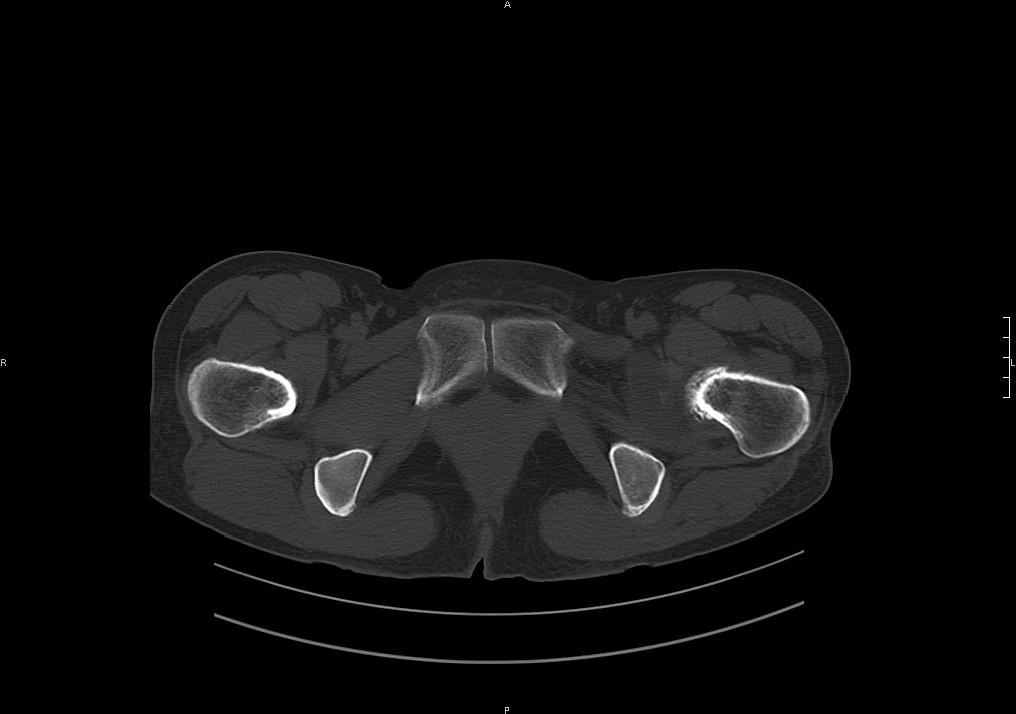

滑膜增厚钙化,关节鼠及滑囊积液,髋臼增生。考虑骨性关节病

滑膜增厚钙化,关节鼠及滑囊积液,髋臼增生。考虑骨性关节病。